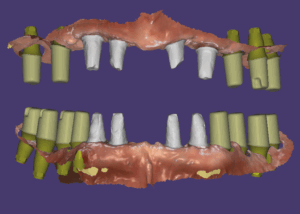

수술후 5개월차에 2차를 진행했습니다. 교합이 불안정해서 이 분은 스캔을 해서 맞춤지대주를 만들고 최종모양의 보철을 PMMA재료로 밀링해서 2차 당일에 끼워드렸습니다.

그렇게 한 이유는 교합안정성을 확보한 후 최종보철을 끼우기 위함이었어요.

고경을 조절해 준 디자인

이분의 경우 치료전 고경이 낮아져 있어 아래턱이 앞으로 나오고 위로 올라가 있어 얼굴이 더 나이들어보이고 주걱턱처럼 보이는 상황이었습니다.

그래서 최종보철을 할 때에는 이 부분을 해소하기 위해 고경을 높여주었습니다.